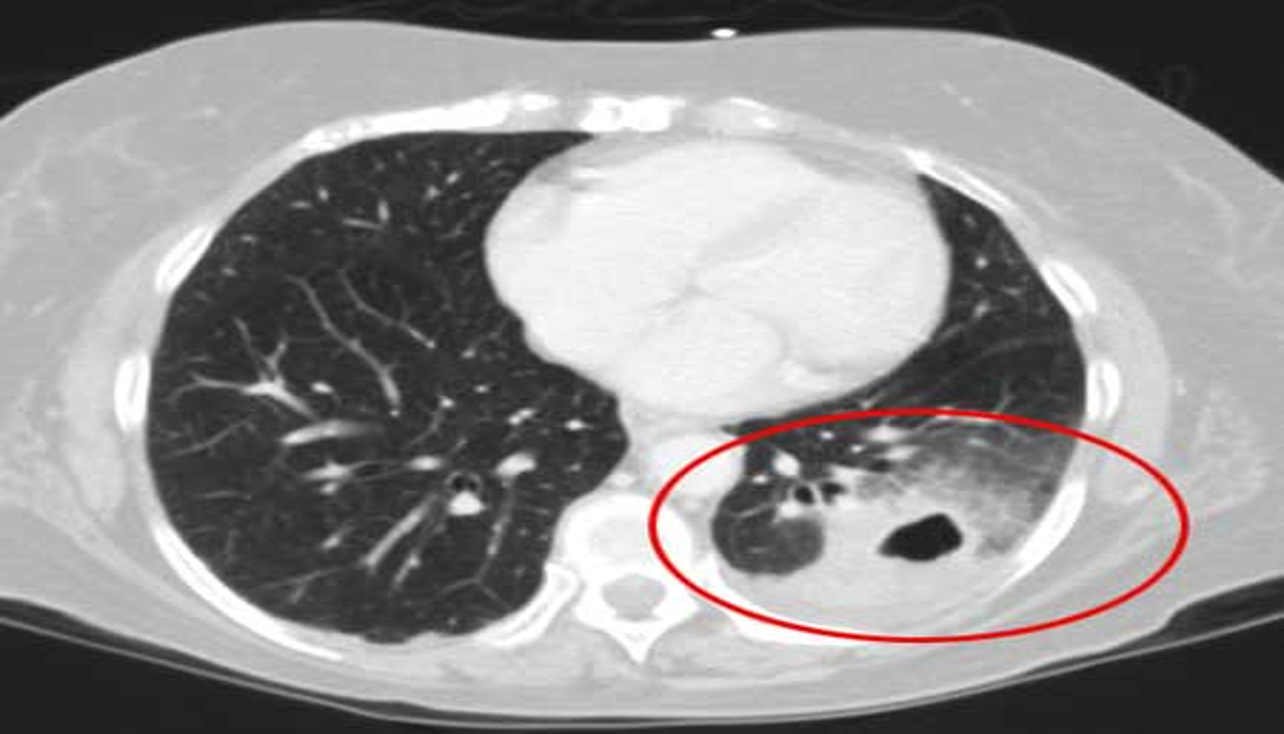

CT scan:

Provides more detailed imaging of suspected abscess or empyema.

CT chest (axial plane; lung window) of a patient with a history of bacterial pneumonia

Opacification of much of the right lower lobe parenchyma is the result of air space consolidation. Pulmonary vessels are obscured and patent airways

(air bronchograms, white dashed line) are seen.